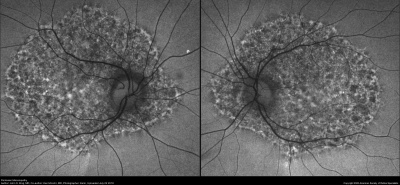

- Intermediate: Characteristic circumscribed nummular areas of RPE loss from the posterior pole to the midperiphery. (See figure.)

- Late: Widespread areas of depigmentation, hyperpigmented plaques, vascular attenuation, and optic atrophy.